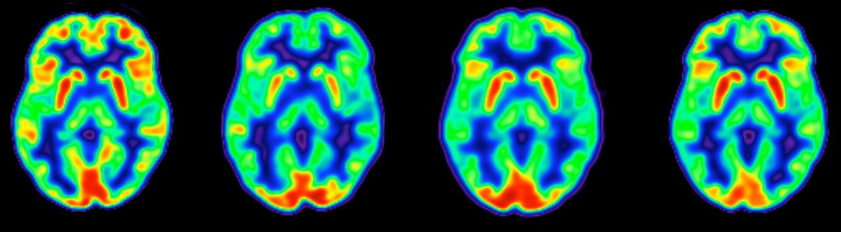

Ende nuk dihet se si ndryshimet gjatë menopauzës ndikojnë në shëndetin e mëvonshëm, por kjo gjendje po tërheq më shumë studime. Gjatë menopauzës dhe perimenopauzës afërsisht katër deri në 10 vjet që çon në periodat e fundit të grave, nivelet e estrogjenit luhaten dhe bien. Estrogjeni mbron trurin femëror nga plakja dhe stimulon aktivitetin nervor. Në studimin e fundit, studiuesit bënë skanerin e trurit të rreth 160 gra të moshës 40 deri 65 vjeç dhe i krahasuan ato me 125 burra të së njëjtës moshë. Studiuesit studiuan trurin e grave që ishin në tre kategori, ato që nuk kishin filluar menopauzën, të përcaktuar si kur një grua është pa perioda për 12 muaj; ato në perimenopauzë dhe ato që ishin në postmenopauzë.

Ndërsa skanimet treguan një rënie në vëllimin e lëndës gri, për disa gra rëniet e tilla u rikthyen pas menopauzës, veçanërisht në “precuneus”, një rajon i trurit i përdorur në njohjen shoqërore dhe kujtesën.